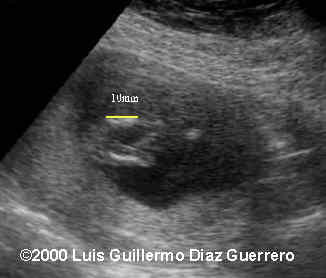

This is a different type of case this time... instead of a great big baby... these are several images from a 12 week old fetus.

Overall view of the baby. What is striking is the shape of this fetus. The most striking finding was the impossibility of seeing the neck of the baby. There is hyperextension of the fetal head with the axis of the face in a perpendicular line with the axis of the fetal body. The head is not well delineated because there is a large occipital cephalocele.

• The abnormal shape of the fetus with no distinct separation between the head and the body.

• The position of the face in relation of the body.

In order for the head to be in such an unusual position, the spine has to be very abnormal, and this was the very difficult part of this case: at 12 weeks the spine is barely visible. If this had been an older fetus, findings a crooked spine with a retroflexed head would have suggested Iniencephaly, which is what this case represented.